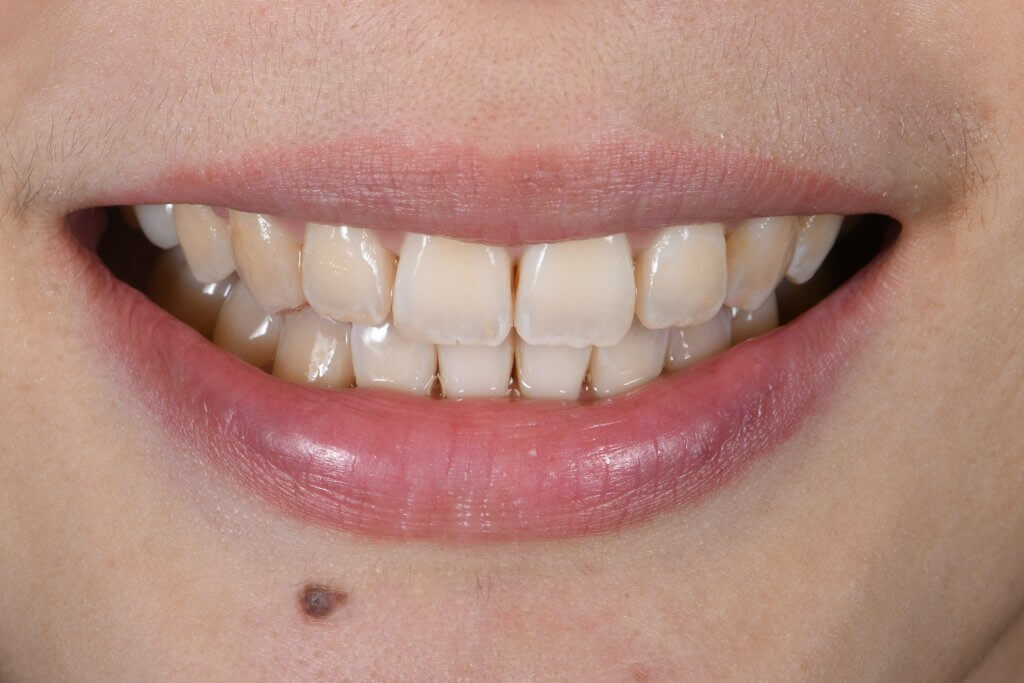

骨性暴牙案例:改善嘴突、笑齦與深咬的綜合治療

- 主要訴求: 改善下排齒列不整齊、中度深咬以及嘴突感。

- 臨床矯正分析: 患者具備明顯的骨性暴牙特徵(更多介紹可參考此文)。上顎骨骼過度向下生長導致笑容時牙齦露出量過多(笑齦),且伴隨中度深咬問題,增加了後收門牙的難度。